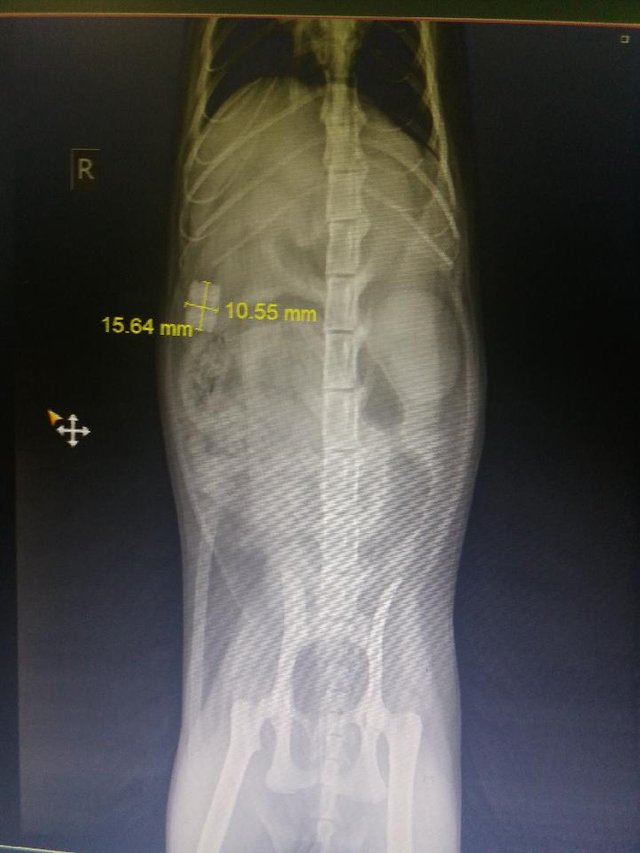

On rendgen situation was clearer - she ate some plastic thing and it’s not in her stomach anymore - it has gone to her small intestine!

Here is the picture they have showed me.

They are guessing it’s a LEGO figure and we all can not believe how it happened!